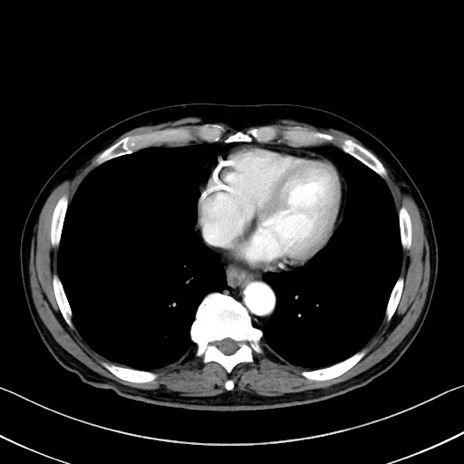

冠状断像